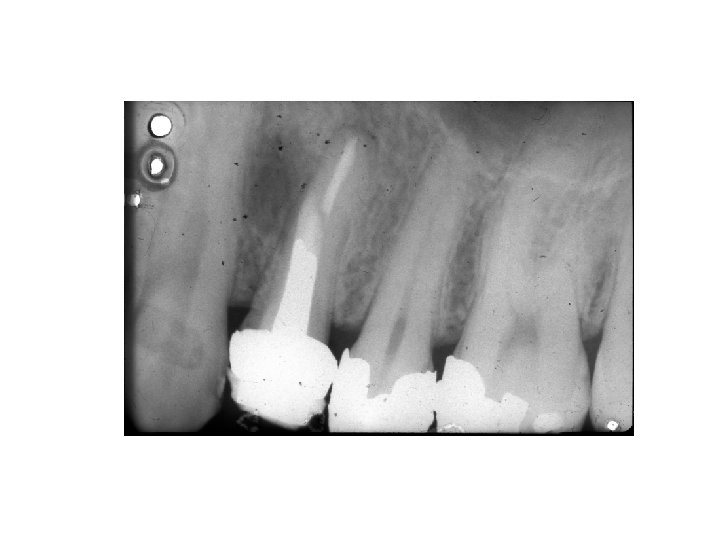

Wurzelbehandlung

Vor der Wurzelbehandlung Nach der Wurzelbehandlung